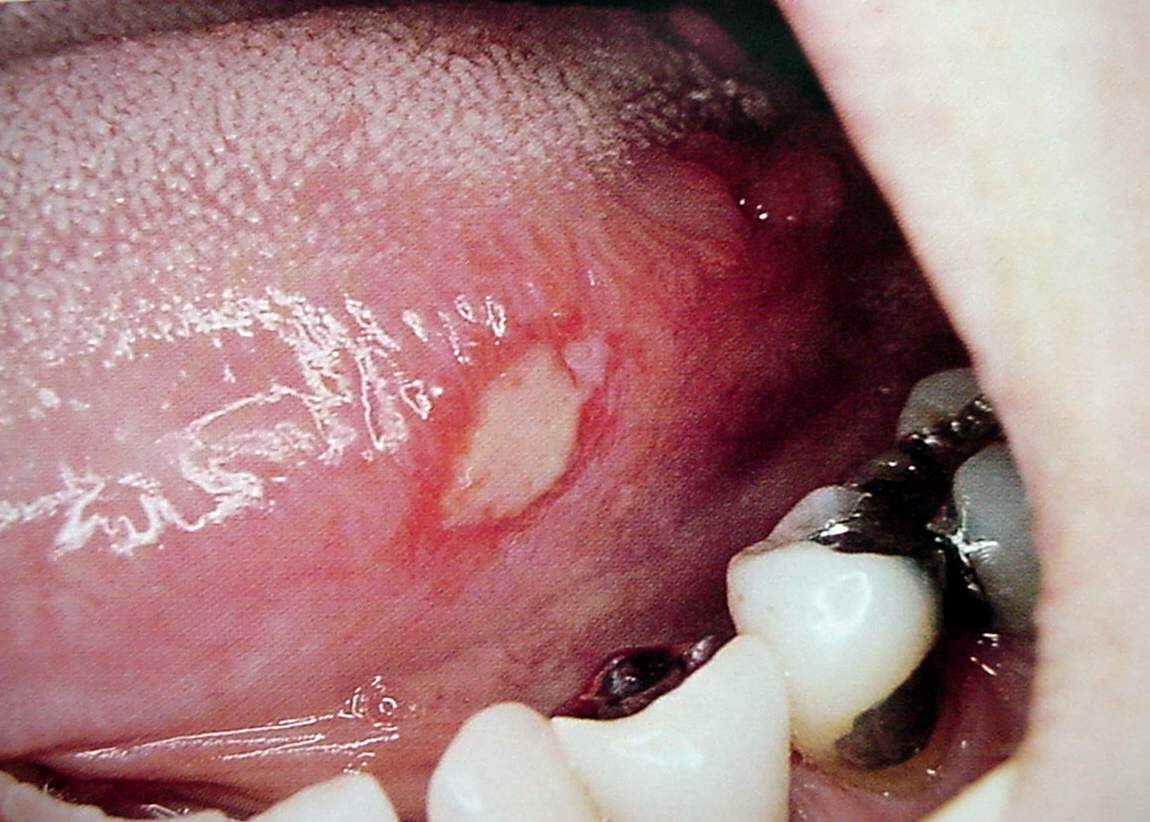

Pharynx and Esophagus Clinical Photos for Static Stations